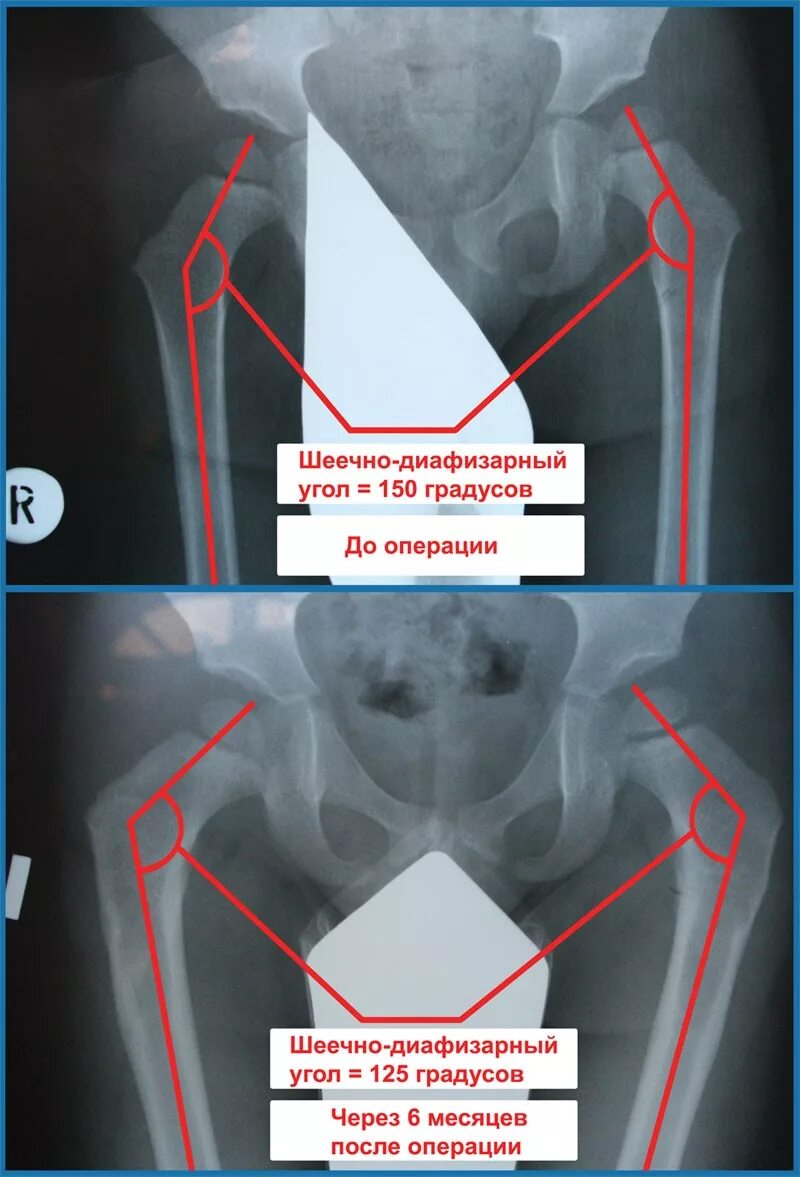

Код мкб дисплазия тазобедренных суставов у детей